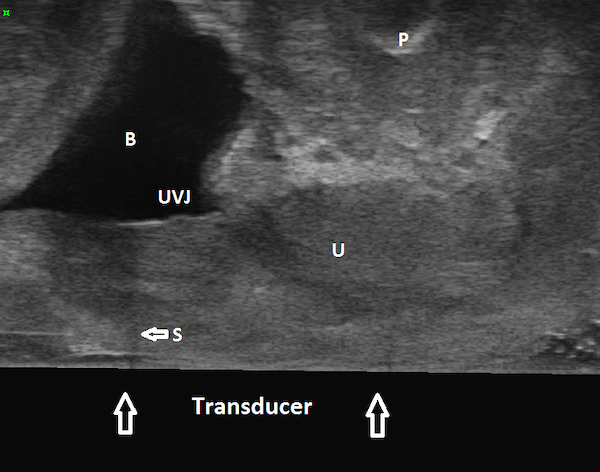

Figures 1, 2, and 3 are mid sagittal plane cut sections of 3D cubes obtained of the anterior pelvic compartment using an endovaginal transducer (BK Profocus Ultraview, Peabody, MA).

Figure 3

Endovaginal 180 degrees anterior compartment image in the midsagittal plane (transducer in the vagina scanning anteriorly): transobturator sling is seen to lie proximal to urethrovesical junction. B: Bladder; U: Urethra; S: Sling; UVJ: Urethrovesical junction; P: Symphysis pubis

The sling can be seen located mid-urethrally in Figure 1, underneath proximal urethra in Figure 2, and proximal to the urethrovesical junction in Figure 3, a year after surgery. Whether sling location impacts surgical outcome is a matter of controversy. Dietz et al (2004) concluded that variations in sling placement have little effect on symptom resolution and patient satisfaction in a study of 142 women whose outcomes were evaluated 5 weeks to 2.1 years following TVT sling surgery. Using transperineal ultrasound, the tape position in their study was found to vary from 30 mm above to 12.7 mm below the symphysis pubis at rest and between 15 mm above to 18.7 mm below the symphysis pubis on Valsalva. However, in an unmatched case-control study of 100 patients who underwent Monarc transobturator sling surgery, our group found that the sling location was significantly more proximal in those who had failed sling surgery when compared with those who had succeeded. In 90% of the patients in whom the sling had favorable outcomes, the sling was found to be located either beneath the āhigh pressure zoneā of mid-urethra or at the junction of the proximal and mid urethra (Hegde et al 2013).

The key differentiator in two studies is the fact that Dietz et al (2004) have used the symphysis pubis as the reference point for determining sling location; they measured the distance of the sling from the symphysis pubis. However, in our study we measured tape percentile (Hegde et al 2013), i.e., the distance of the midpoint of the sling from the urethrovesical junction divided by the urethral length. We found that when we determined sling location with respect to the urethral length, location had a significant impact on surgical outcomes.